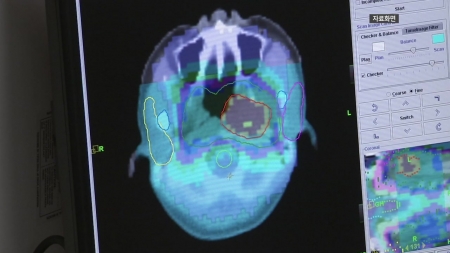

지난해 암 사망, 전체 24%...'40대 유방암·50대 간암·60대 이상 폐암' 사망률 1위

지난해 사망 원인으로 암이 1위를 기록한 가운데 40대는 유방암, 50대는 간암, 60대 이상은 폐암 사망률이 가장 높은 것으로 나타났습니다.

폐암과 간암, 대장암, 췌장암, 위암 순으로 사망률이 높았습니다.

연령대별로는 40대는 유방암, 50대는 간암, 60대 이상은 폐암 사망률이 가장 높았습니다.

40대는 유방암 사망률이 2년 연속 1위를 기록했습니다.